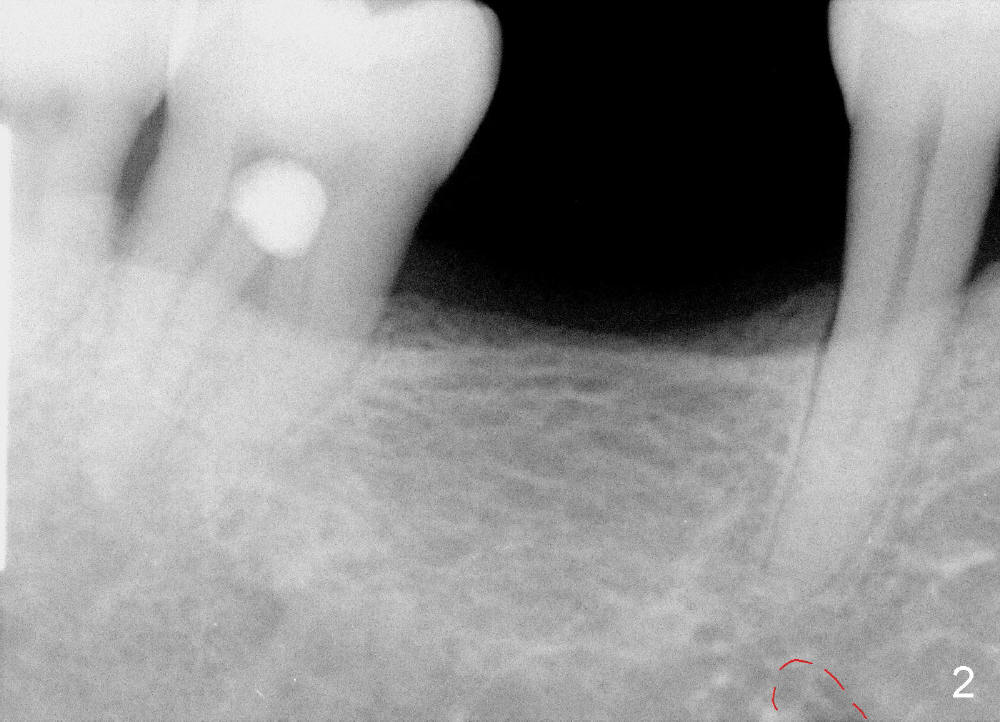

It is critical to identify the inferior alveolar canal (IAC) prior to and during implantation. A 59-year-old man requests implant for the lower right 1st molar (Fig.1). PA taken with a regular sensor holder does not show IAC except part of the mental loop (Fig.2 red dashed line), whereas the one taken with an endo sensor holder does show IAC (Fig.3 yellow dashed line).